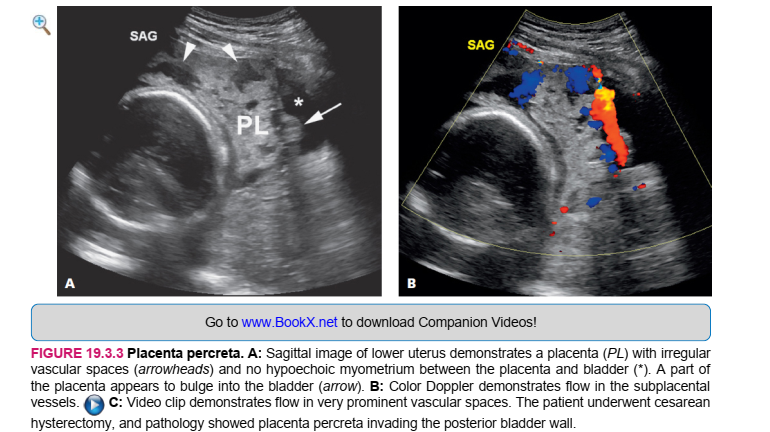

The possibility of accreta or increta should be raised when an anterior previa is seen on ultrasound in a woman who has had one or more cesarean deliveries. The diagnosis can be made with a high degree of confidence in such a woman if ultrasound demonstrates absence or thinning of the myometrium beneath the placenta and/or large, irregular vascular lacunae. Percreta is diagnosed sonographically when the placenta extends through the serosal surface of the uterus (Figure 19.3.3). This is seen most clearly when the placenta protrudes into the bladder. Placenta accreta, increta, or percreta is most often diagnosed sonographically when it is located in the anterior lower uterine segment. The diagnosis, however, can also be suggested in other locations within the uterus when there is thinning or absence of the myometrium beneath the placenta, together with irregular vascular lacunae (Figure 19.3.4).

HÌNH 19.3.3 Placenta percreta. A: Hình ảnh sa tử cung dưới tử cung chứng tỏ nhau thai (PL) không đều

khoảng trống mạch máu (đầu mũi tên) và không có myometrium giảm âm giữa nhau thai và bàng quang (*). Một phần của nhau thai xuất hiện phình vào bàng quang (mũi tên). B: Doppler màu thể hiện dòng chảy trong nhau thai tàu thuyền. C: Đoạn phim chứng minh dòng chảy trong không gian mạch rất nổi bật. Bệnh nhân được mổ lấy thai cắt tử cung và giải phẫu bệnh cho thấy nhau thai bám vào thành sau bàng quang.